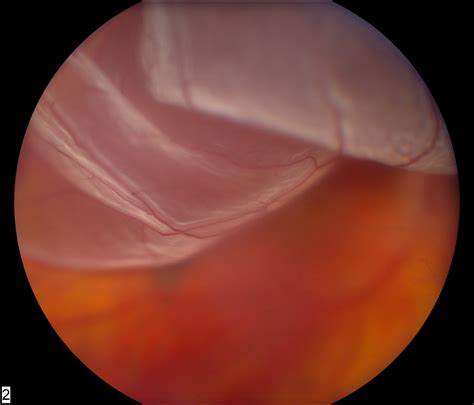

Dezlipirea de retină este o afecțiune oculară care apare atunci când retina se desprinde de peretele ocular, din cauza acumulării de lichid subretinian.